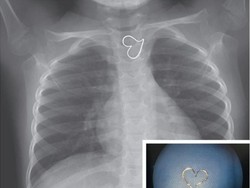

Sebuah foto rontgen kembali viral. Foto lama yang sebenarnya sudah beredar sejak 2005 itu menampilkan struktur pembuluh darah di telapak tangan yang tak biasa.

Jatuh cinta sering disimbolkan dengan jantung hati. Simbol ini pula yang muncul saat seorang bocah menjalani pemindaian sinar X. Tandanya sedang jatuh cinta?